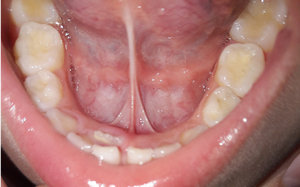

Дочке 7 лет, возраст, когда молочные зубки выпадают. Начал шататься верхний второй зуб слева. Сегодня заметила, что рядом режется зуб, но только совсем не там, где я его ожидала.

Подскажите, можно ли будет как-то исправить ситуацию? Он как-то совсем не там, где нужно растет. Причем, жалоб от нее не поступало, ничего не болело. Честно, я в панике, хочется, чтобы у девочки были красивые, ровные зубки. Что делать?